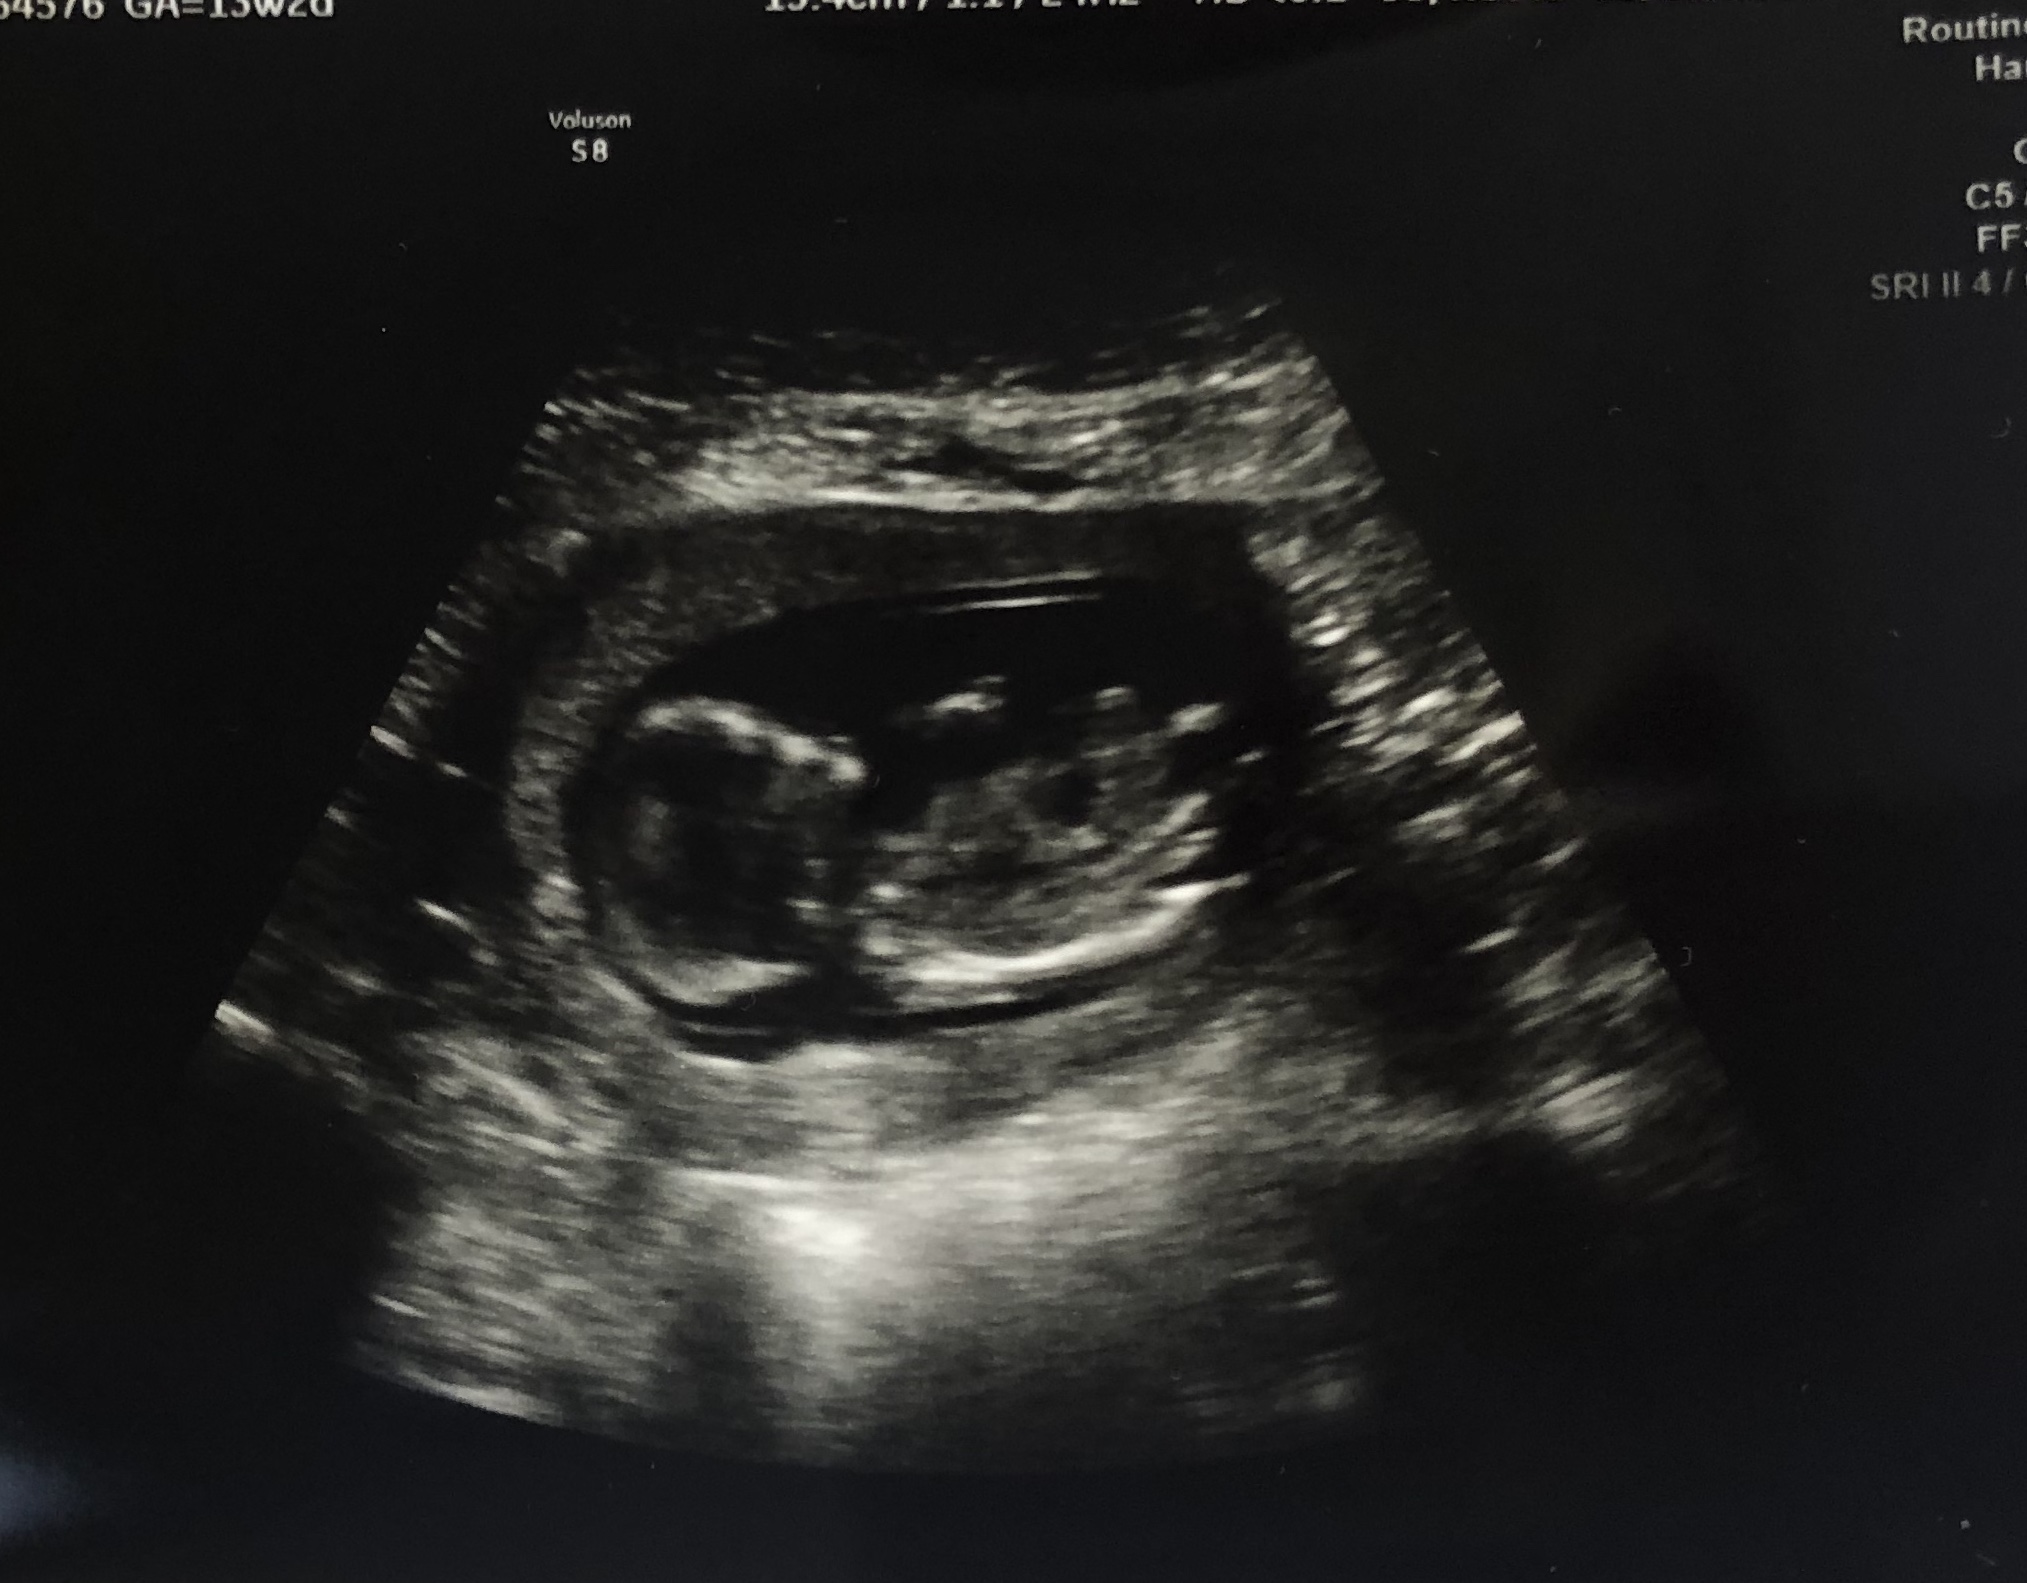

SECOND TRIMESTER. PUMPED. This week was SOO good. SOOO good, y’all. Got to see baby and hear the best sound in the WHOLE world, I don’t think I will ever get tired of that perfect sound. Rookie Rod’s heart is beating strong and they are GROWING and measuring big. The best part? BABY IS SUCH A WIGGLE WORM!!!!! It was so crazy to see Baby L wiggling all over the screen, I hope they keep that up so I can feel kicks soon. I am so antsy for all the fun the second trimester brings and ready to announce the gender…I get way too close to slipping up every time I sit down to type out another bump date HAHA! But in all seriousness, everyday that passes and this baby grows bigger and bigger…my heart is just so full and grateful. Also, seeing Austin hear the heartbeat and see baby wiggling around for the first time was something so surreal and so beyond words. It made everything just feel so much more happening and it was such a happy day. We celebrated by going out to our first restaurant since MARCH…which was also a HUGE treat. Rookie Rod wanted ALL the Texas roadhouse rolls…so thats where we went! Nothing else really to report, I still feel amazing, but do get REALLY cranky if I am not eating…(sorry Bubs)! Baby is the size of a muffin now and has all their parts and is now just growing and growing. Thankful for each and everyday.

Also, it feels really good to put the first trimester anxiety behind us, as easy as it was physically…there was that mental game of trying not to let anxious thoughts ruin the happy. I didn’t realize the weight I had been carrying until going in for my scan this week and hearing everything looks PERFECT and so HEALTHY. Healthy is my new favorite word I think! My tummy is also FINALLY starting to resemble a little bump and not just a big bloat, so that has been SO EXCITING!!!!! Thank you to each of you for following on this journey! It makes me feel SO LOVED and supported!!